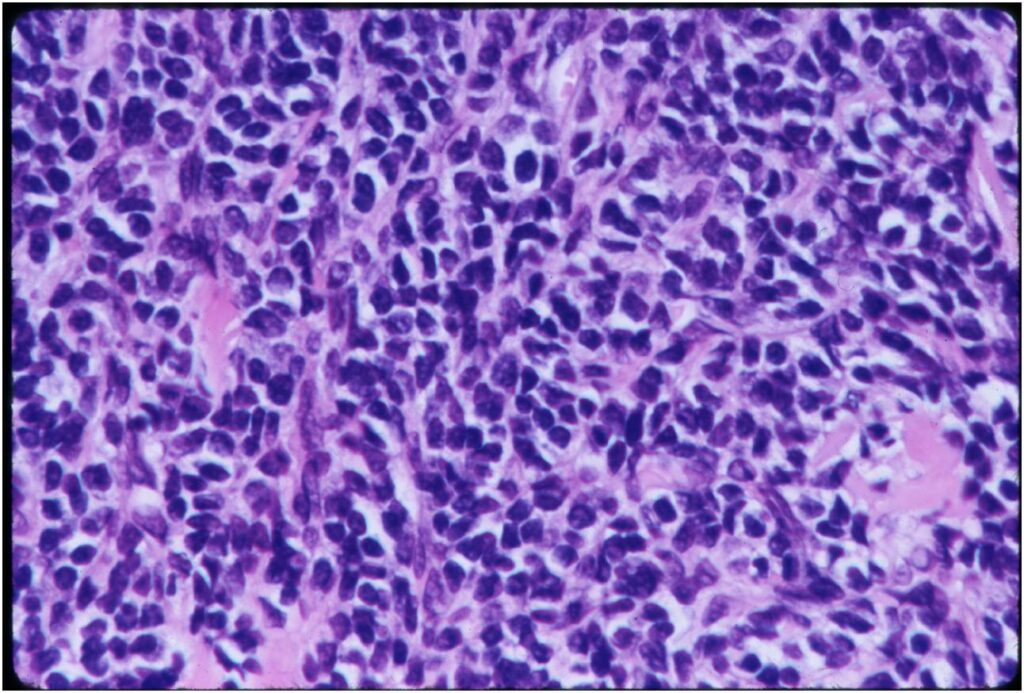

Microscopic Pathology

- Neoplastic cells may be small, round, oval, or spindle shaped

- Undifferentiated mesenchymal cells similar to Ewing sarcoma

- Low grade islands of cartilage scattered throughout the mesenchymal cells

- Usually only a small part of lesion

- Cytologically low grade

- Usually sharply demarcated from surrounding stroma

- Stain S-100 positive

- Cells within cartilage

- Tend to have round or ovoid nuclei

- Lacunae are poorly formed

- May contain islands of collagen resembling osteoid

- Lesions are vascular and often have large, anastomosing vessels that impart hemangiopericytoma-like pattern